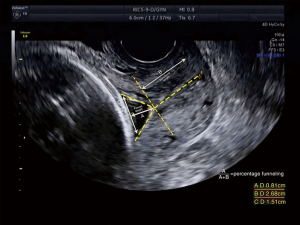

Cervical funneling was considered present when sonography showed ballooning of the membranes into a dilated internal os with a closed external os and protrusions of at least 15% of the entire CL (23,24) (Figure 4).